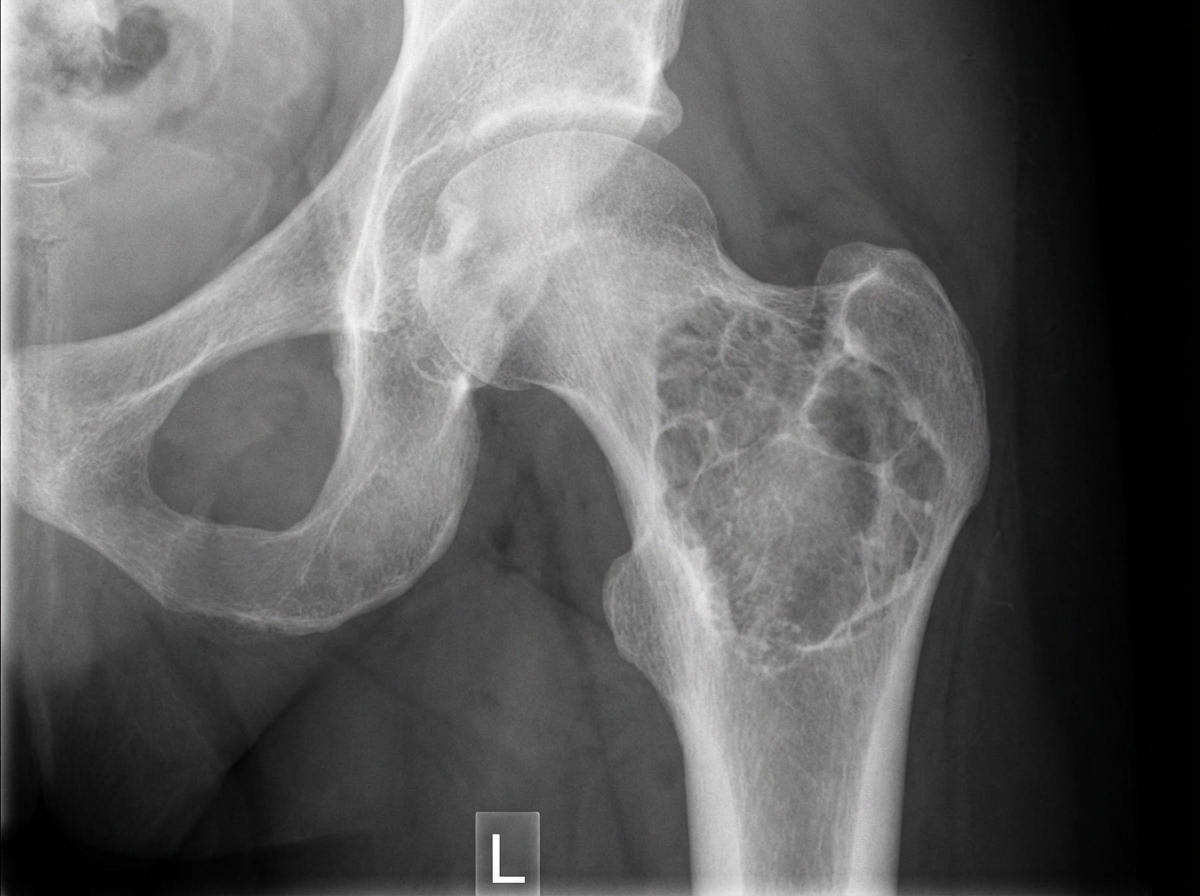

A 30-year-old male presented with hip pain for the last 6 months. A hip X-ray is provided. What is the likely diagnosis?

Explanation: ***Giant cell tumor*** - Typically occurs in the **epiphyseal region** of long bones in patients aged **20-40 years**, matching this 30-year-old male presentation. - Characteristically presents as an **eccentric lytic lesion** with a **soap-bubble appearance** on X-ray, commonly affecting the **proximal femur** near the hip. *Simple bone cyst* - Usually affects **younger patients** (children and adolescents) and occurs in the **metaphyseal region**, not the epiphysis. - Presents as a **central, well-defined lytic lesion** without the eccentric location typical of giant cell tumors. *Adamantinoma* - Predominantly affects the **tibia** (85-90% of cases) rather than the hip region. - Shows **biphasic histology** with epithelial and osteofibrous components, and typically occurs in the **diaphysis**. *Ewing's sarcoma* - More commonly affects **younger patients** (10-20 years) and typically involves the **diaphyseal region**. - Characteristically shows **onion-skin periosteal reaction** on X-ray, which is not typical for hip lesions in 30-year-olds.